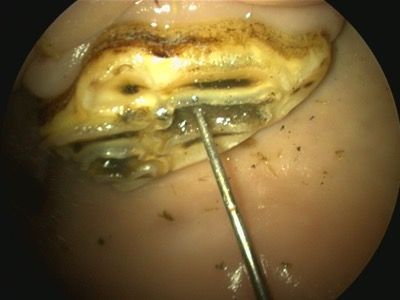

The most common type of dental caries (occlusal exposure of developmental infundibular hypocementosis) identified in equine teeth is maxillary CT infundibular cemental caries (Figure 3A). If left untreated, this can progress to septic pulpitis or pathological fracture.9 In most cases, treatment consists of debridement and filling with dental material to prevent further evolution of the tooth decay. To summarize, necrotic, impacted food material must be removed from the infundibulum using dental picks and a high-speed dental drill or burr (Figure 3B). The infundibular cavity is then flushed, and disinfectant solutions such as dilute sodium hypochlorite or chlorhexidine are flushed into the cavity preparation (Figure 3C). A layer of a single step-etch bonding product is applied to the cavity walls, and the cavity is filled with a dual-cured flowable resin composite.10-12 (Figure 3D)